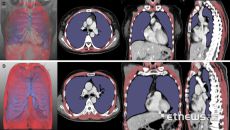

서울대병원, 흉부 CT 기반 루게릭병 예후 예측인자 확인 “폐활량검사 한계 보완”

서울대병원 연구팀이 루게릭병 환자의 호흡 기능을 정밀하게 평가할 수 있는 새로운 영상 기반 검사 지표를 개발했다. 기존 폐활량- 2025-06-23 11:28